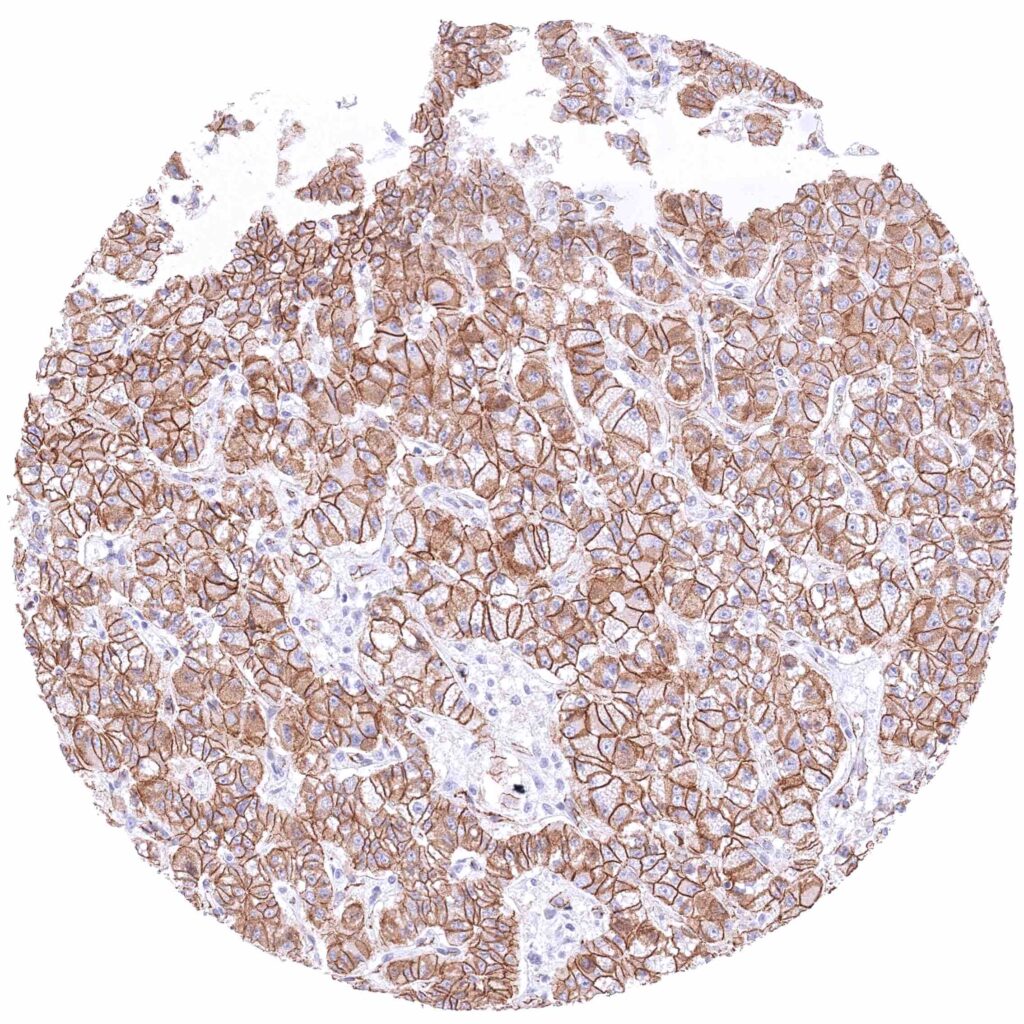

Prostate – Adenocarcinoma (Gleason 3+3=6) with strong membranous β-Catenin staining of tumor cells.